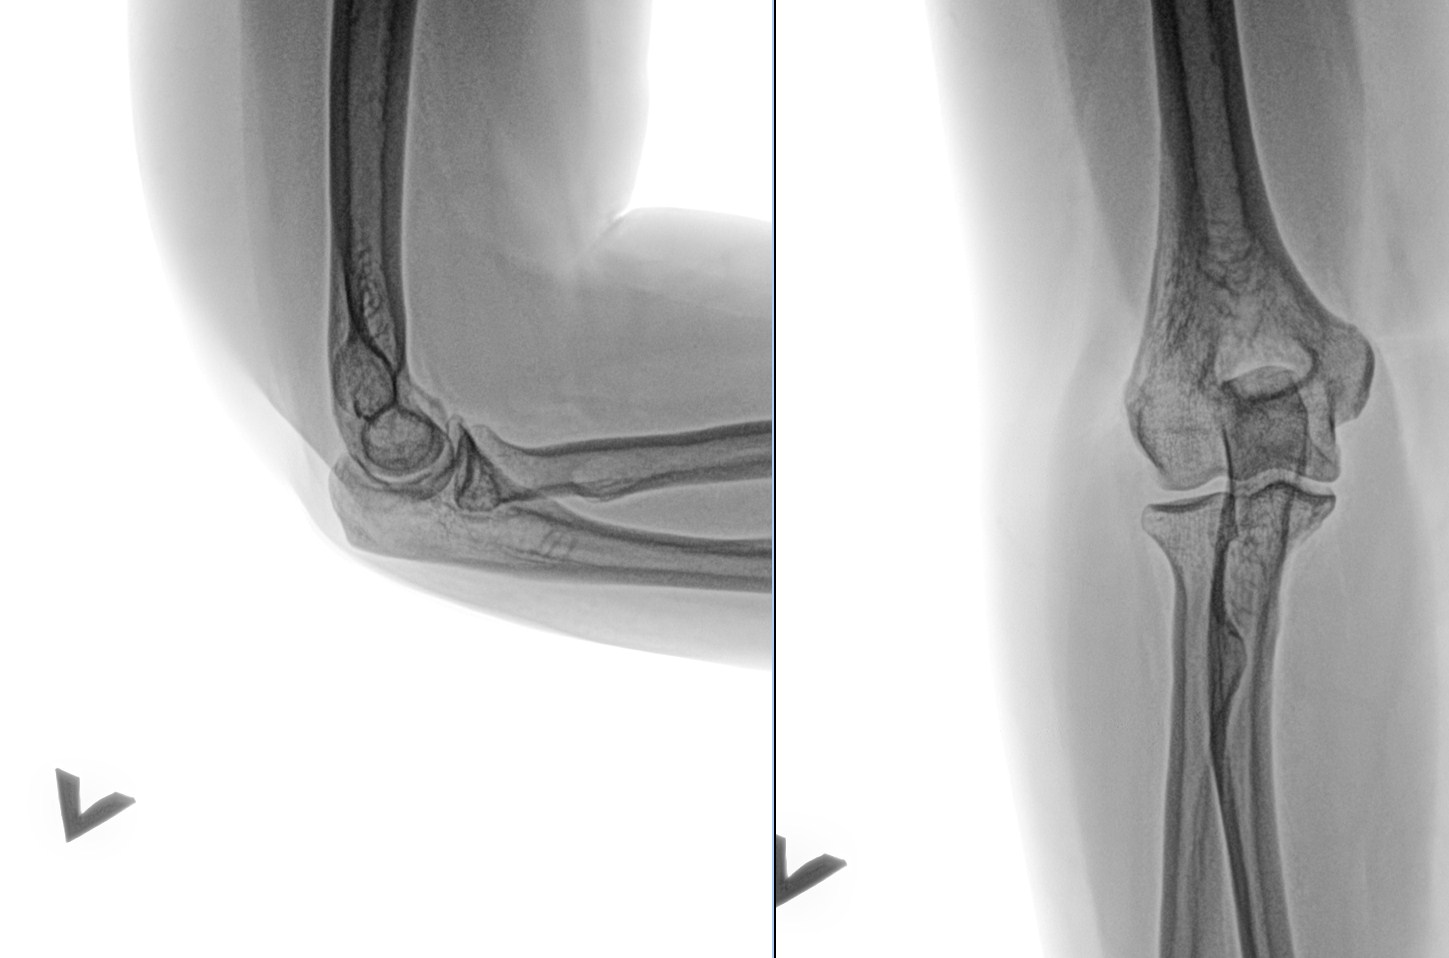

Радиоульнарный угол: строение и особенности лучевой кости